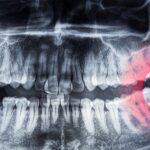

wisdom teeth

Pediatric X-rays use specialized digital technology and child-specific parameters to minimize radiation exposure while providing accurate diagnostic images. Dr. Christine Yeojin Kim creates comfortable experiences for children through age-appropriate explanations and child-friendly environments in Manhattan.